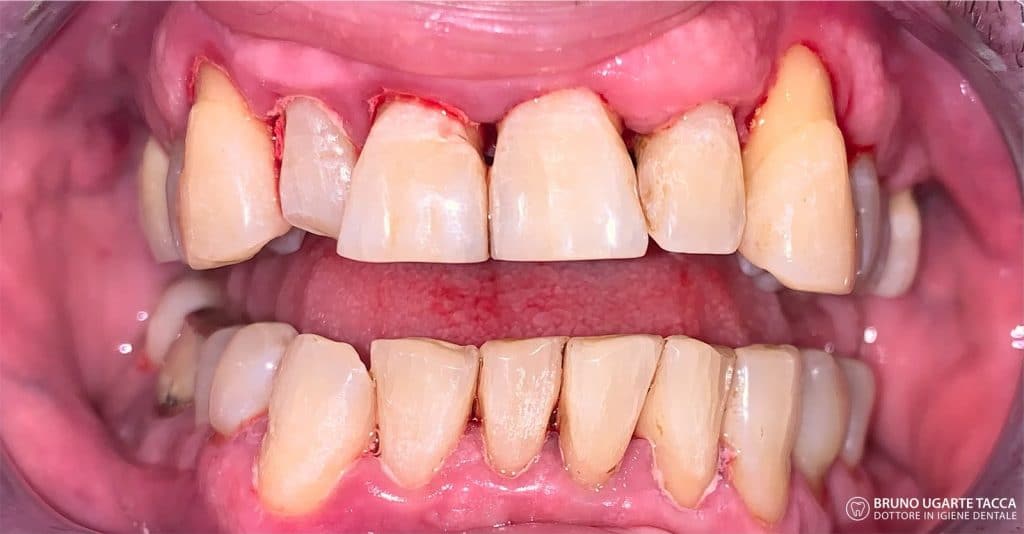

Performing the complete instrumentation

supragingival and subgingival with ultrasonic and / or manual instruments in one

single session or in two sessions at most performed over 2 days